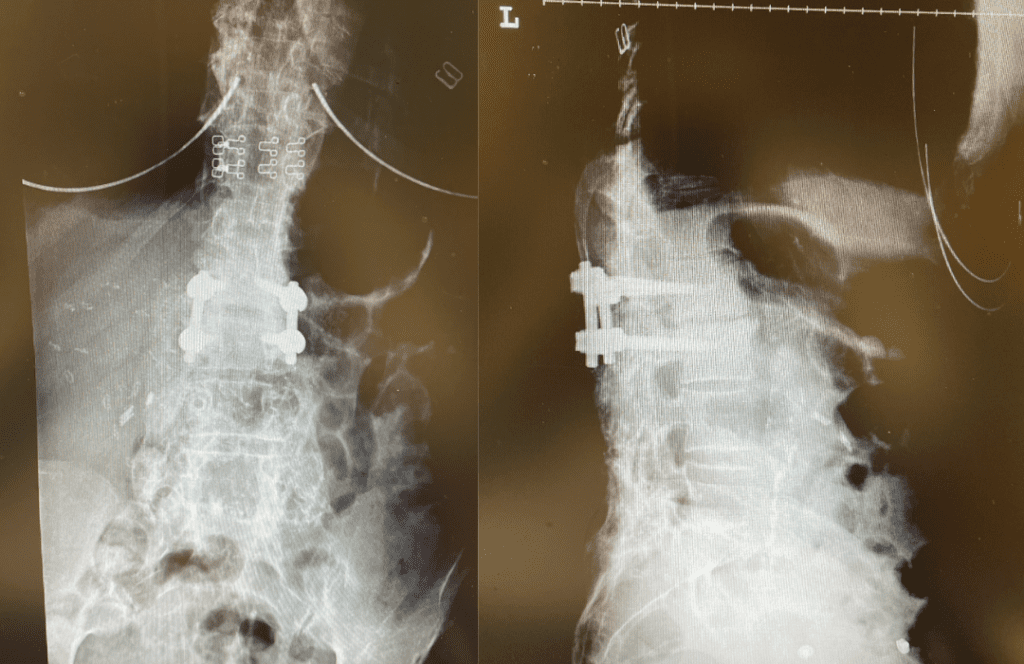

Figure 3. Post Op AP and lateral x-rays after L2-3 instrumented fusion